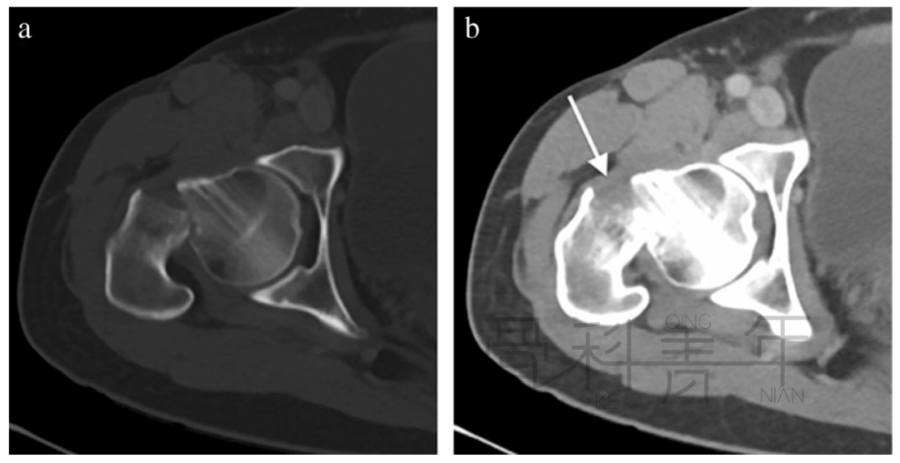

病例4 股骨颈骨折,在CT横断面骨窗上未见明显液体分层(a),在软组织窗(b)可见高密度血肿影(箭头所示,CT值为50HU)。

病例5 股骨颈骨折,在CT横断面软组织窗上可见在髂腰肌内出现积脂血症表现。